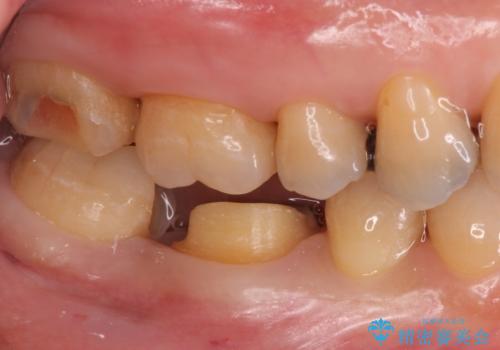

- 右下奥歯の詰め物が取れたとのことで来院されました。

セラミックでの治療をご希望されましたが、残っている歯が少なかったためクラウンでの治療を行いました。

もう一つ奥の歯に関してもセラミックにやり替えたいとのことでしたので、こちらはインレーでの治療を行いました。

- 右下6:仮歯+セラミッククラウン/11,000円+110,000円 右下7:セラミックインレー/77,000円費用は治療当時の料金となります

残る歯が薄かったり、十分な量を確保できない場合はクラウンで治療した方が今後の破折リスクを抑えることができます。